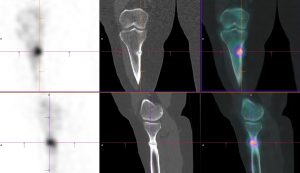

Hyperfixations en regard d’encoches corticales radiotransparentes perpendiculaires à l’axe de l’os, des métaphyses fémorales bilatérales et de la métaphyse tibiale droite (en zones portantes).

Aspect typique de stries de Looser-Milkman, spécifiques de l’ostéomalacie.

Stries de Looser-Milkman (fractures de stress chez les patients atteints d’ostéomalacie)